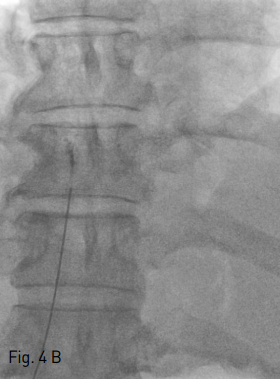

Fig 4A

Intraportal entry was confirmed by contrast injection on fluoroscopy (A).

Fig 4B

Under sonographic and fluoroscopic guidance, the needle was advanced into the left hepatic vein (B).